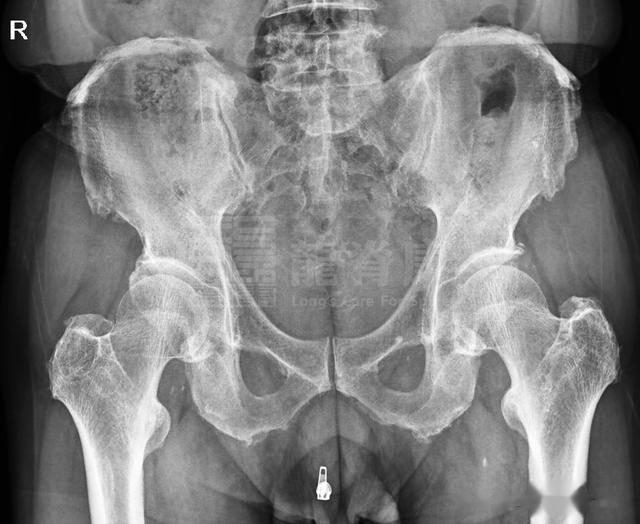

2、X光片检查

腰椎生理曲度存在,腰椎3-4椎体可见骨桥形成,多棘突偏歪;两侧髂骨略呈左高右低,右宽左窄,骨质增生明显,髂骨边缘可见毛糙影。